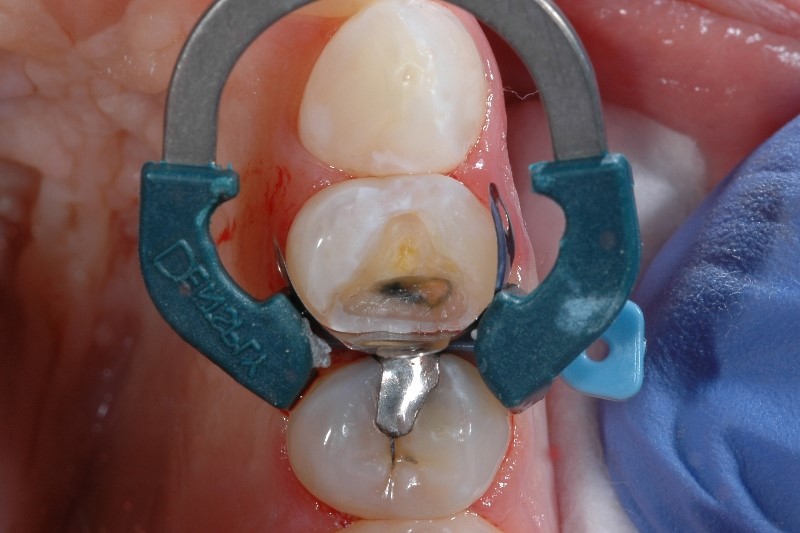

What causes post-op sensitivity after composite fillings? Quite a few things, actually - placing composite resins is a complex procedure considering the nature of dentin is close to the pulp, and some studies have estimated sensitivity occurs after 10-15% of posterior composite restorations.1

The most common causes of postoperative sensitivity can be narrowed down to:

Studies4 have shown that polymerization shrinkage of the resin is one of the top causes of sensitivity post-op, but that’s not the only scenario where incomplete material coverage can lead to post operative sensitivity. It’s important to cover the internal surface completely and uniformly with an adhesive. You’ll know you’ve done this correctly if the surface appears glossy rather than matte.